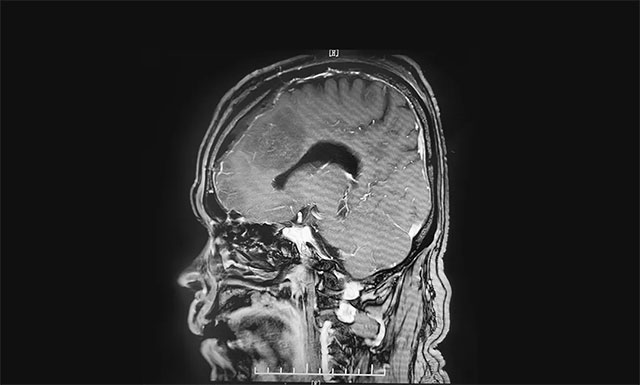

▲ 術(shù)后影像顯示腫瘤被切除

術(shù)前,神經(jīng)外科團(tuán)隊制定了詳實(shí)的手術(shù)方案。6月2日,在征得家屬同意后,神經(jīng)外科團(tuán)隊為患者進(jìn)行了左側(cè)額部大腦鐮旁腦膜瘤切除手術(shù)。

術(shù)中可見腫瘤起源于大腦鐮并跨越兩側(cè),在顯微鏡下,李士其教授在吳治群博士、黃秀夫醫(yī)生及醫(yī)護(hù)團(tuán)隊協(xié)助下,憑借精湛的手術(shù)技巧和豐富的臨床經(jīng)驗(yàn)對腫瘤進(jìn)行精細(xì)剝離。在充分保護(hù)好上矢狀竇、中央?yún)^(qū)的靜脈回流的前提下,經(jīng)過5個多小時的手術(shù),最終腫瘤被順利切除。術(shù)后的病理結(jié)果顯示是良性腦膜瘤。